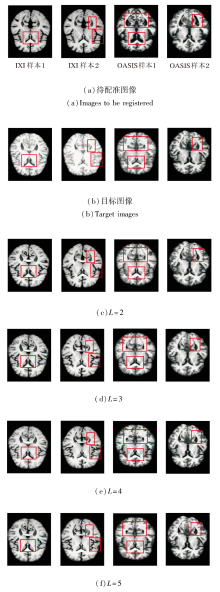

为此, PyraMLP-Net采用4个编码层与4个解码层构成的四级金字塔结构, 实现由粗到精的渐进式配准.为了验证该层级设计的有效性, 以网络层级数L=4为基准, 对比L=2, 3, 5时的性能表现.

在IXI、OASIS数据集上各选取2个样本, 当网络层级数L改变时, 得到的图像配准结果如图11所示.L对PyraMLP-Net性能的影响如图12和表8所示.

由图11、图12和表8可见, 当L=2时, 网络深度不足, 导致多尺度特征提取不充分, 对细微解剖结构的匹配能力有限, 配准精度最低.L=3时, PyraMLP-Net能捕获更多的中等尺度特征, 性能优于两层网络, 但仍难以建模高分辨率细节.L=4时, PyraMLP-Net实现从低分辨率到全分辨率的完整特征覆盖, 能更精准地匹配解剖结构, 各项指标值均显著优于浅层结构.当L=5时, 其性能与4层网络相比未出现明显提升, 但计算开销显著增加.以IXI数据集为例, 单次运行时间从0.355 s增至0.418 s, 内存占用从14.823 GB升至16.018 GB.这表明对于具有典型分布和结构规律的脑部MRI数据, 4层网络已能充分学习其特征表示, 继续增加层数不仅无法带来性能增益, 反而会引入冗余参数并降低计算效率.

综合配准性能与资源效率, L=4能在满足精细解剖结构匹配要求的同时, 避免因层级不足或过度而导致的性能损失或计算资源浪费, 实现最佳平衡, 从而验证PyraMLP-Net四层架构的合理性.